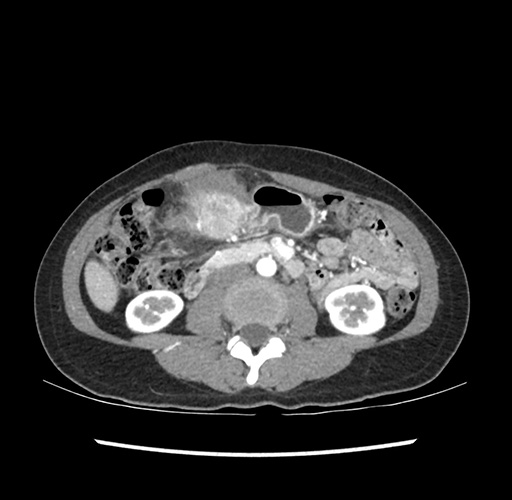

Imaging Analysis

Look through the patient's CT scan to identify any areas of concern for the necessary procedure.

Based on your CT findings, which issue(s) would give reason for "planned slowing down moment(s)" in this case?

Considering a standard left lateral sectionectomy procedure, what step(s) of the operation would you do differently in this case ?